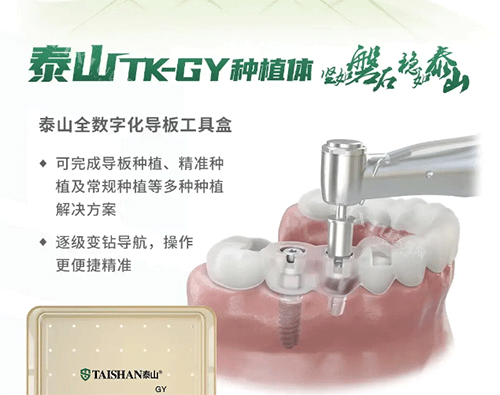

很多网友分享过纠结过程——缺了一颗牙,医生会问选种植牙还是烤瓷牙。种植牙是在缺牙位置的牙槽骨里植入钛合金“人工牙根”,等3-6个月和骨头长稳后,再装牙冠;烤瓷牙则要把缺牙两边的健康牙齿磨小一圈,做个连在一起的“桥体”,把假牙固定在磨小的邻牙上。

价格差异是很多人纠结的点。种植牙单颗费用在8000-20000元(含种植体、基台、牙冠),具体看品牌(比如瑞典诺贝尔、瑞士ITI更贵);烤瓷牙单颗桥体费用500-8000元(材质不同,镍铬合金便宜,全瓷牙贵),但因为要做3颗(缺1做3),实际总费用可能和种植牙接近甚至更高。